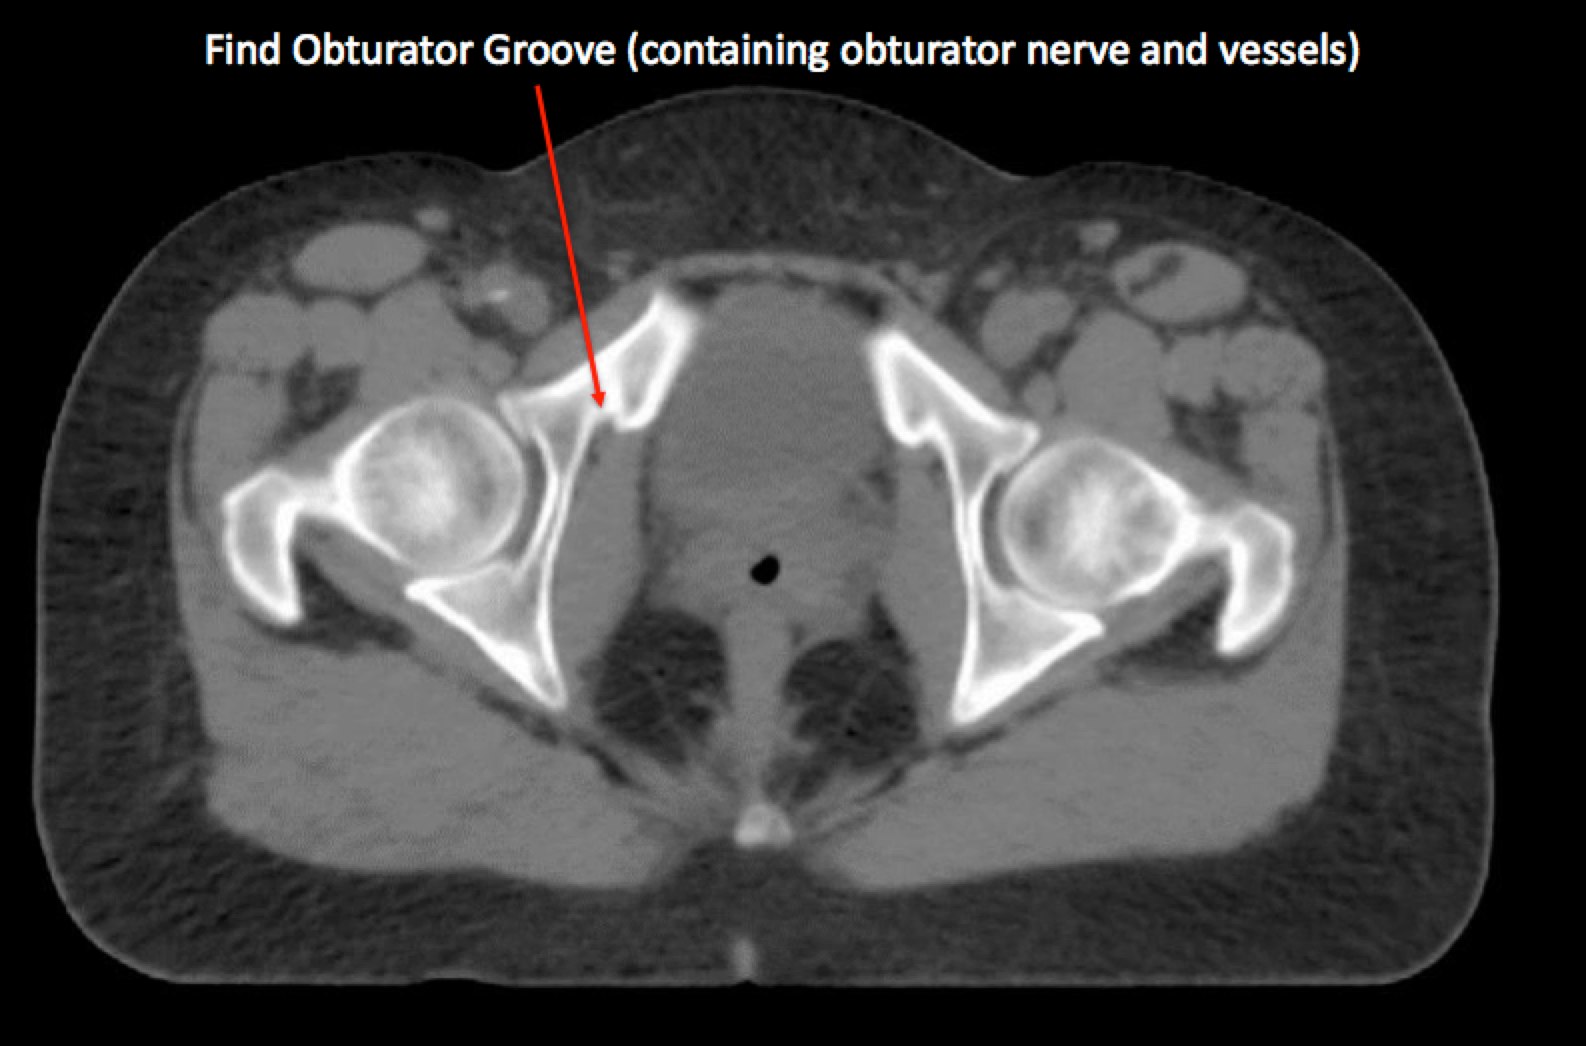

To identify the obturator nodes the following landmarks may be used. (Note: this works for any pelvis where one wishes to find the obturator nodes):